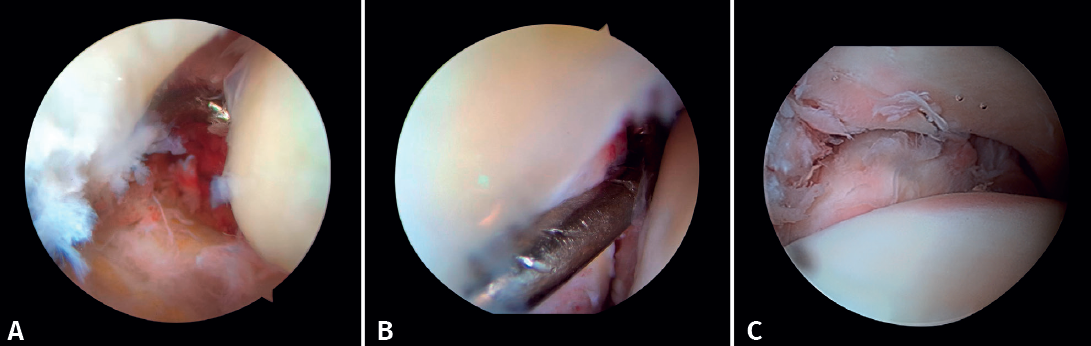

Figura 6. A: lesión de sindesmosis; B: control de la reducción para evitar la sobrecorrección; C: control intraoperatorio de la correcta reducción del peroné en la incisura.

- Diagnóstico de inestabilidad sindesmal: la artroscopia permite la evaluación de la integridad de la sindesmosis y del ECM sobre la radiografía y la TC, sobre todo en la clasificación de las fracturas SER II y IV. Se ha demostrado que la evaluación radiográfica no siempre predice la lesión sindesmal. Además, la artroscopia permite asegurar una reducción anatómica de esta. Takao encontró que el 87% (33/38) de los tobillos con fractura tenían lesiones de la sindesmosis detectadas por artroscopia(20).

La artroscopia permite la visión directa de la sindesmosis y, además, permite su evaluación dinámica(22,21).

- Nos permite diferenciar entre fracturas SER II (en las que no debería existir lesión sindesmal) y fracturas SER IV, en las que sí hay afectación de la sindesmosis, pudiendo estabilizarla(5,23).

- Puede evitar la falsa impresión de un espacio articular medial ensanchado en la fluoroscopia debido a anomalías congénitas.

- Poder visualizar la incisura maleolar junto con el control radioscópico nos permite asegurar un correcto posicionamiento del peroné en la incisura fibularis, sobre todo en las lesiones inestables en las que existe riesgo de mala reducción por acortamiento o rotación del peronéa(5,24).

- Evitar la hipercorrección de la sindesmosis, que es muy artrogénica(5,24) (Figura 6).

Xie mostró que la estabilización de la sindesmosis con un sistema de fijación dinámico ofrece resultados funcionales equivalentes y menos complicaciones en comparación con la fijación con tornillos(28). La RAFIAA permite evaluar la congruencia articular tras la reducción anatómica tanto de la sindesmosis posterior como de la sindesmosis anterior. Permite también evaluar la sobrecorrección que puede producirse al comprimir en exceso la mortaja, que ha demostrado ser muy artrogénica(29). Durante la reducción de la sindesmosis nos ayudamos de un palpador que deberemos poder introducir una vez fijada la sindesmosis.